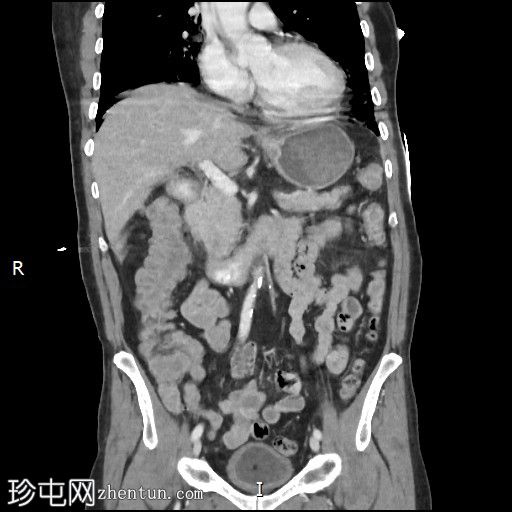

冠状位增强扫描

门静脉期

十二指肠第三段造影剂积聚

活动性出血